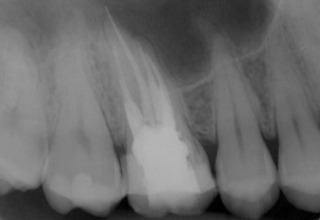

Patient N.M. wünscht eine Drittmeinung, zwischenzeitlich hatte er bereits einen zweiten Zahnarzt konsultiert. Dieser bestätigte eine insuffiziente Wurzelfüllung und vermutete eine Instrumentenfraktur im mb1 (Abb. 1).

Röntgenbefund

Mittels Röntgenaufnahme lässt sich ein frakturiertes Instrument in mb1 vermuten. Des Weiteren scheint es, als sei der distale Wurzelkanal sowie der mb2 nicht abgefüllt worden, was sich zu einem späteren Zeitpunkt der Behandlung bestätigen sollte. Der Patient wurde vom vorbehandelnden Zahnarzt über die Fraktur nicht aufgeklärt.